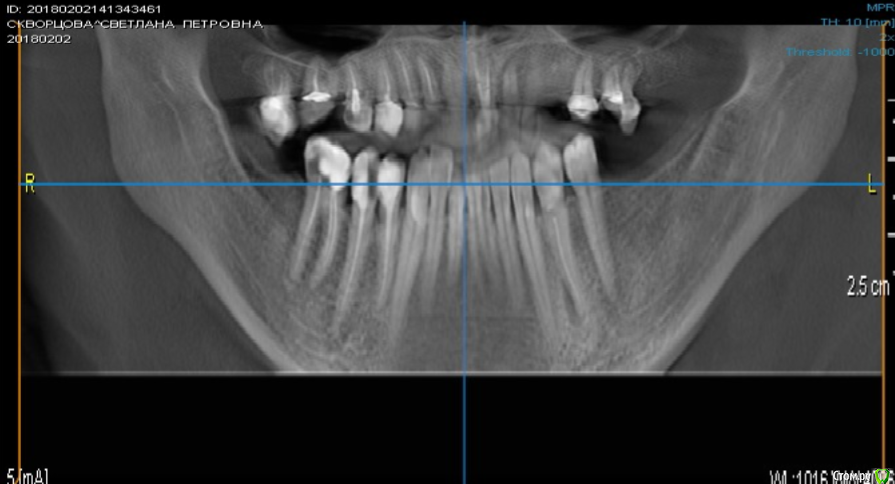

scvo 70 Опубликовано 24 октября, 2018 Автор Поделиться Опубликовано 24 октября, 2018 Общий КТ до лечения?Общий КТ до лечения.pdf Ссылка на комментарий

scvo 70 Опубликовано 24 октября, 2018 Автор Поделиться Опубликовано 24 октября, 2018 (изменено) общий КТ 1 фото до лечения Изменено 24 октября, 2018 пользователем scvo 70 Ссылка на комментарий